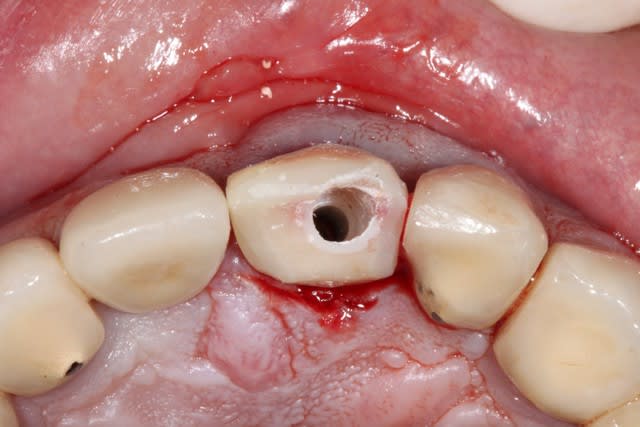

2/ extraction + forage lingualé

3/ pose d'un implant Dentium SuperLine 5/14 en ménageant un espace avec l'os vestibulaire

4/ comblement avec de l'osteon de l'espace vestibulaire, mais aussi d'un autre espace

cet espace est une poche sous périostée qui est créé en vestibulaire de l'os vestibulaire, il faut évidemment ne pas déchirer le périoste.

5 et 6/ Pose d'un pilier en peek et couronne provisoire transvissée